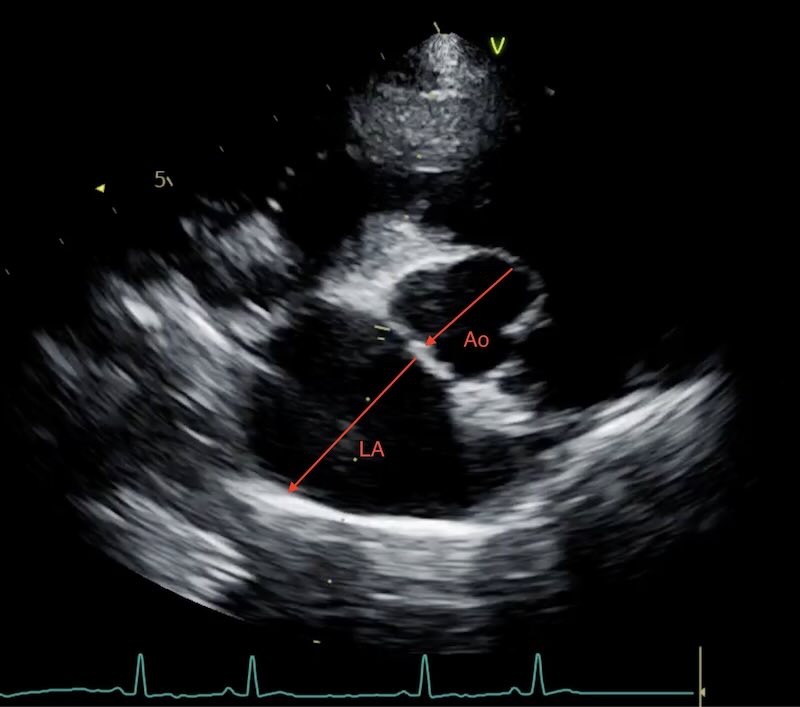

Cats can have their heart ‘tipped’ a long way forwards, creating a lot of variation in the position of the ‘long axis’ and ‘short axis’. This is especially pronounced in older cats. In addition a rotation effect often means the LA:Ao measurement ends up being quite a vertical one:

Also cats sometimes enlarge their atrium in length rather than width. In cats, we use the “Rule of Thirds” for a quick subjective check: on a long-axis view, the left atrium should occupy roughly one-third of the total length of the heart silhouette. If the atrium looks like it is dominating the image, or if it has lost its “square” shape and become globular, the cat is at high risk for blood stasis and ATE.